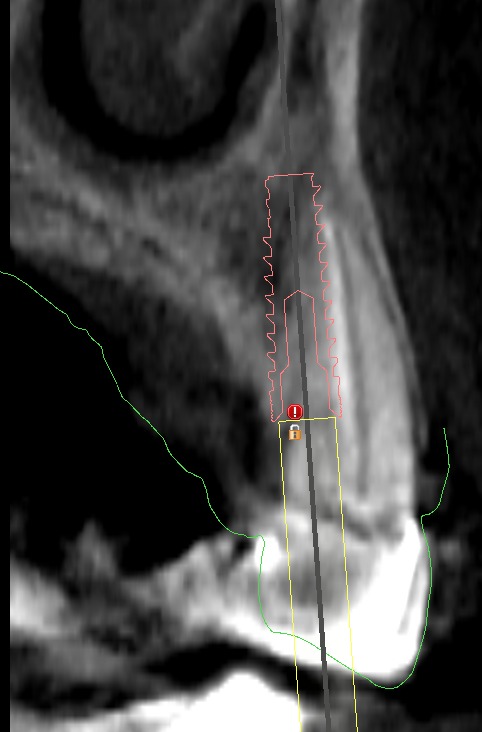

| Corte para-axial vs posición implantaria ideal. |